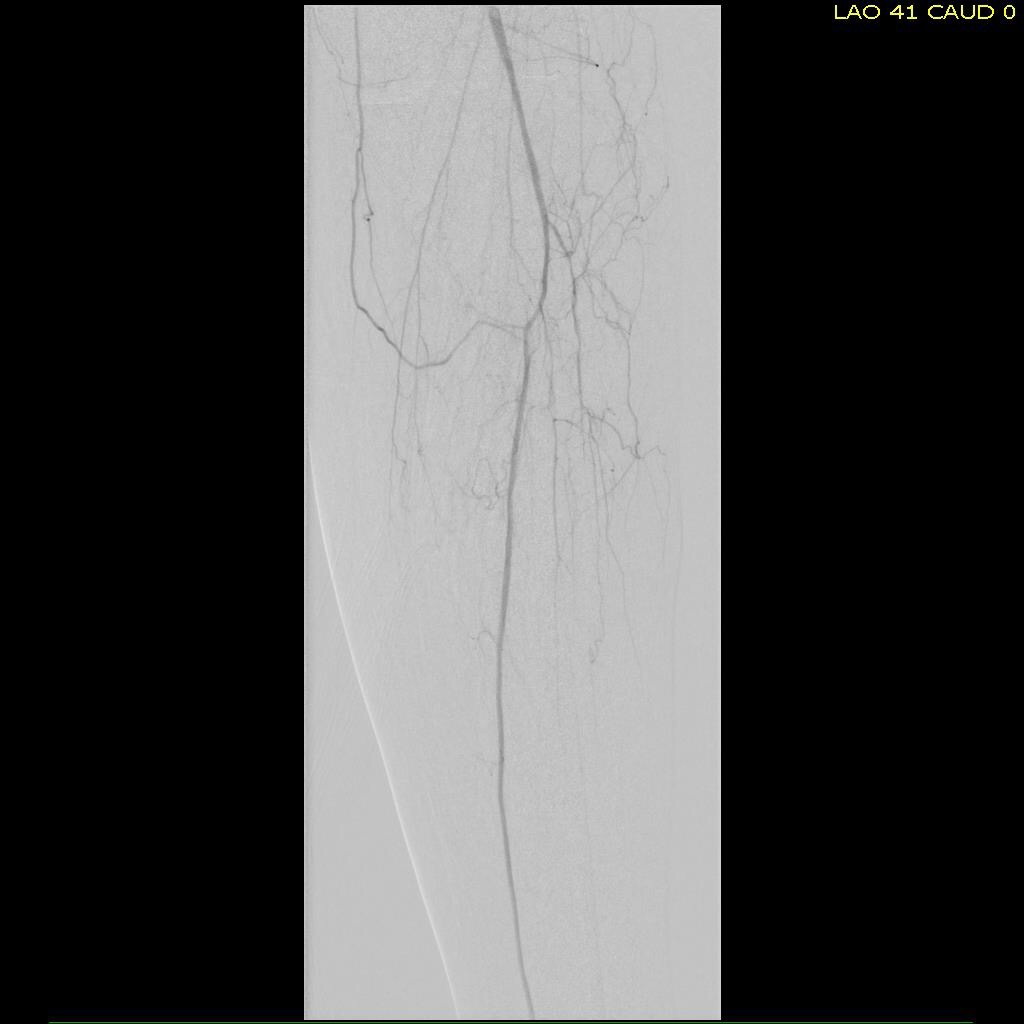

Let me show you one of the first cases I did after returning to Cleveland. I am now practicing at Fairview and Avon Hospitals, premier flagship hospitals in the Cleveland Clinic fleet, on Cleveland’s west side, and a patient arrived while I was on call with sudden onset of pain in his leg from a lack of blood flow. He had occlusive atherosclerotic plaque extending from his external iliac artery to the above knee popliteal artery causing ischemic rest pain.

I contacted LeMaitre Vascular and got in touch with your representative, L. Fisher, who promptly sent the Moll Ring Cutters I needed to perform a remote endarterectomy of the patient’s occlusive external iliac and superficial femoral artery plaque. The technical details of remote endarterectomy are have been covered in my blog (https://vascsurg.me/?s=endore), but in the end, through a 7cm incision in the groin (don’t believe the hype, this is minimally invasive), I restored his arteries to their original open condition. Shown below are the results. It was with great sadness that I heard that the LeMaitre Vascular equipment being sent were the last of the stock available in North America. The patient did very well, with the operation completed well before lunch, and is recovering rapidly from his small wound and big rescue. He gets to walk out of the hospital on two legs, but also with the surety that he avoided a major bypass operation, and avoided the short term gains of stenting from the aorta to the profunda -more peel packs and landfill items and a dubious long term durability. Hey, I even used a XenoSure patch on the common femoral.